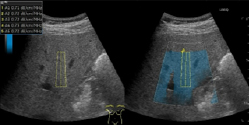

・造影超音波検査

主に肝臓の腫瘍性病変の質的診断や存在診断を目的として行われています。ソナゾイド(ペルフルブタン)造影剤を静脈内に投与して、腫瘍性病変内の血流動態や、肝臓のクッパー細胞という貪食細胞への取り込みを観察し、評価します。

ソナゾイド造影剤による肝腫瘍の評価